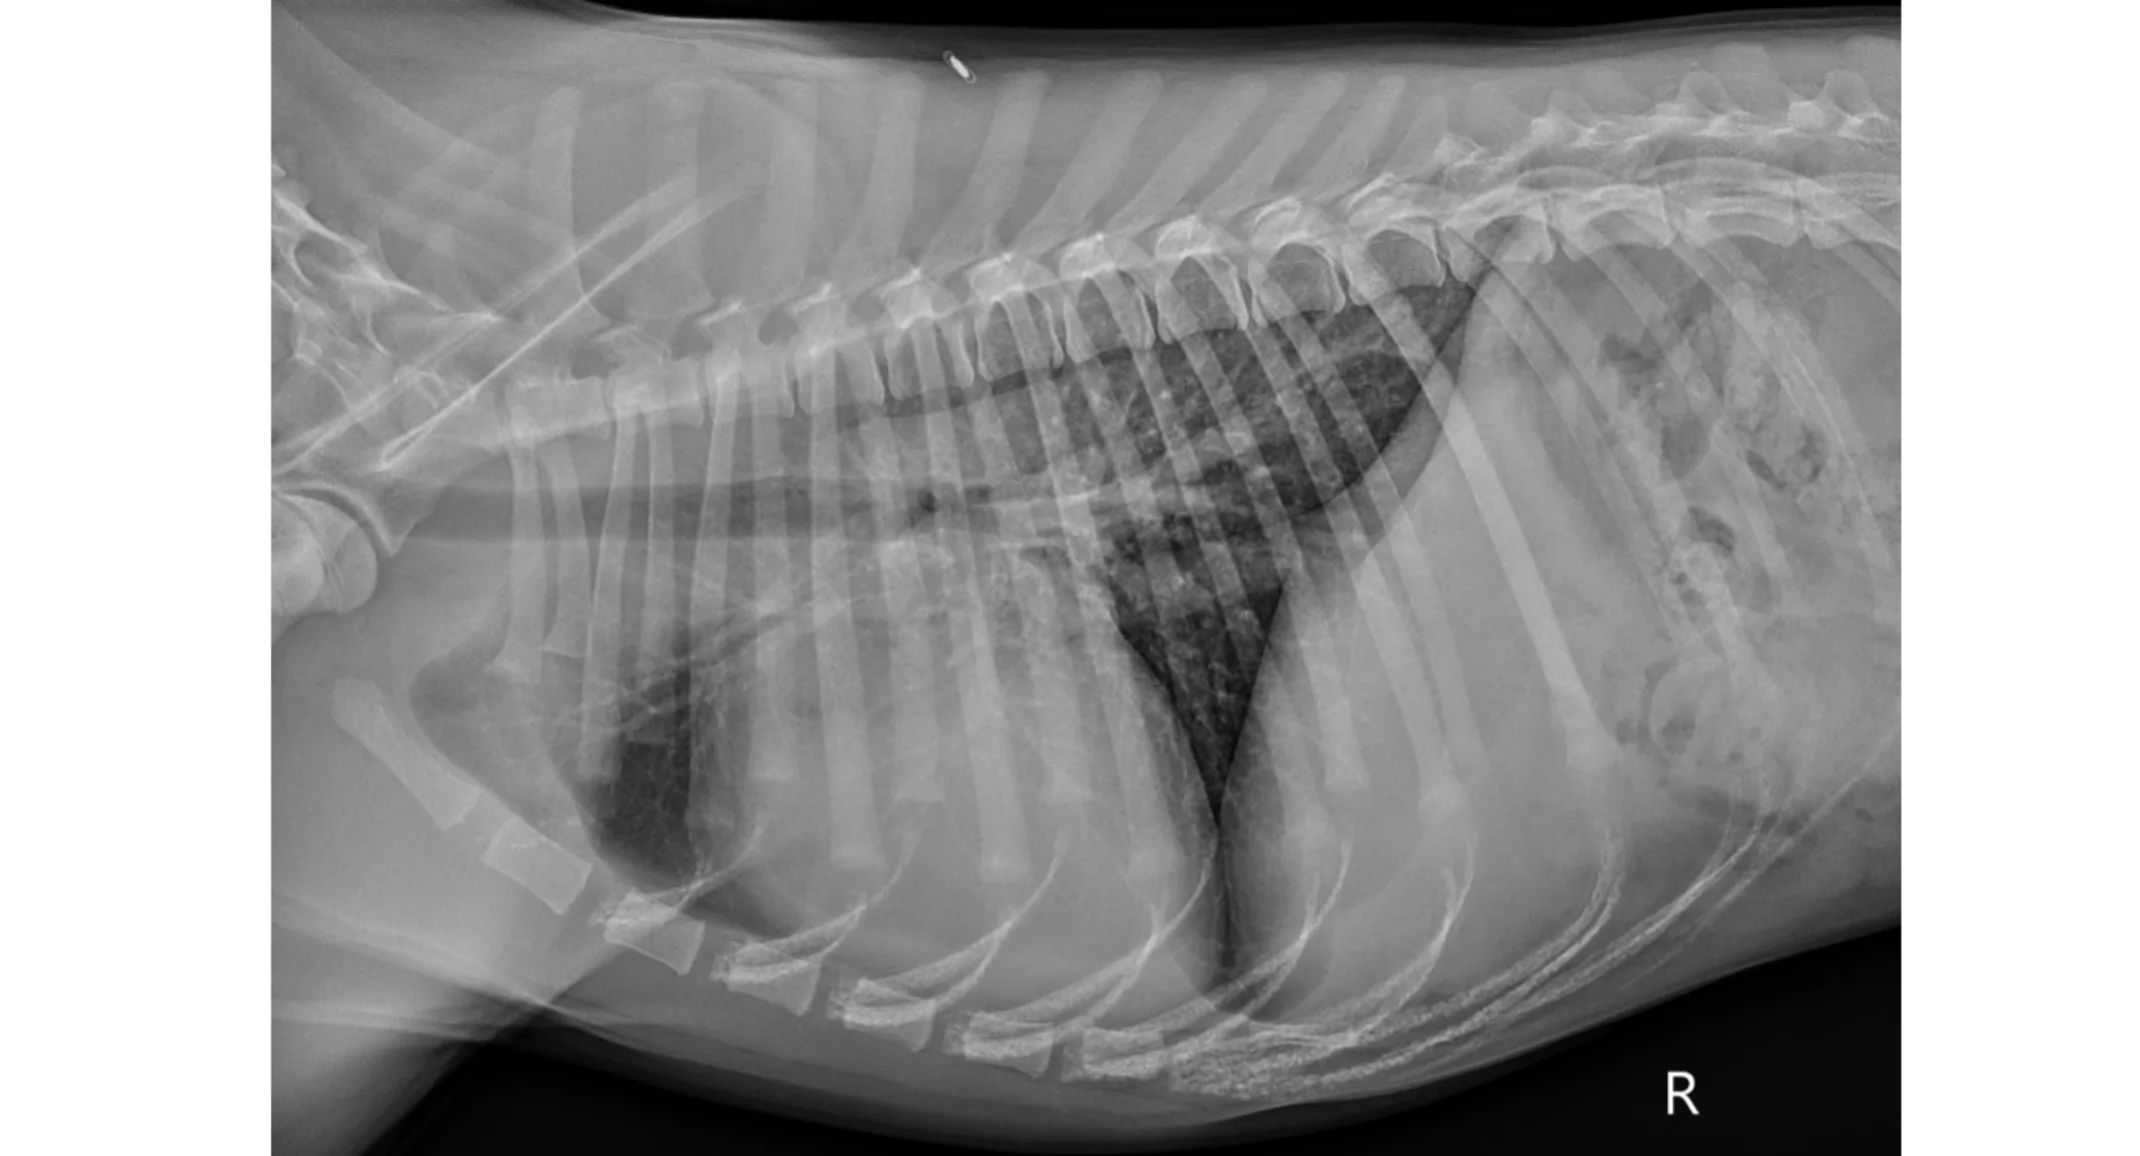

Pre-operative thoracic radiographs (Figure 1): Marked cardiomegaly with pulmonary vascular overcirculation. A mild diffuse bronchial pattern is noted. No evidence of left-sided congestive heart failure.

PICTURE: Figure 1: Pre-operative right lateral thoracic radiograph.